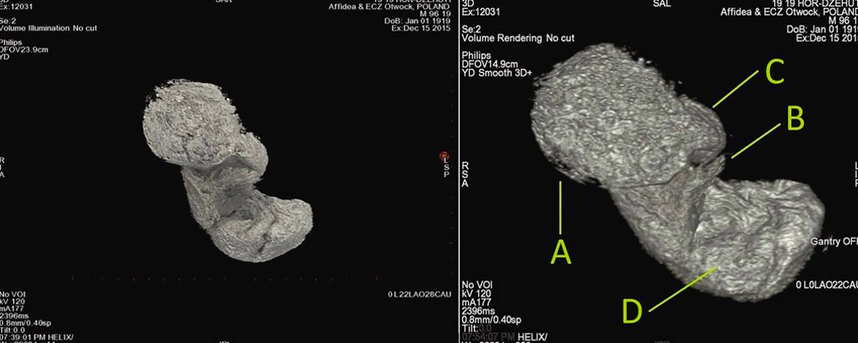

Буквой А на КТ плода обозначена голова зародыша, буквой В – рука Фото: Warsaw Mummy Project